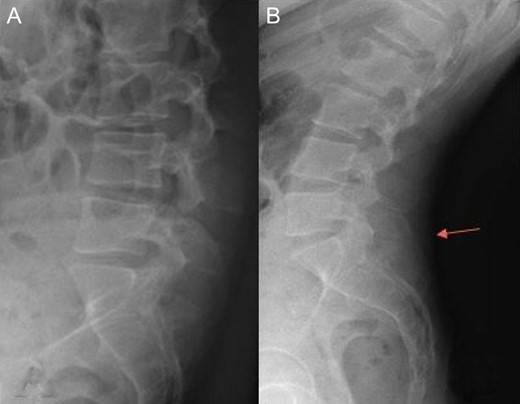

Radiography of the spine revealed an asymmetry of pelvis (Fig. 1), and despite a report refuting Baastrup’s disease, we can see a contact between spinous processes of L5 and S1 in extension (Fig. 2).

Radiography of lumbar spine in anterior-posterior and lateral views showing asymmetry of pelvis.

Radiography of lumbar spine (A: flexion, B: extension). We can see a contact between spinous processes of L5 and S1 (arrow).